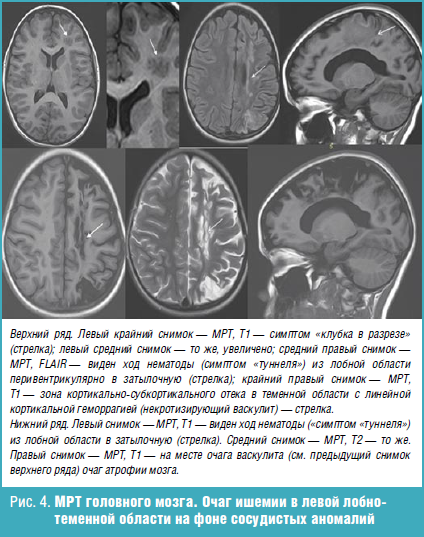

Что такое паразитарная инфекция мозга - фото презентация